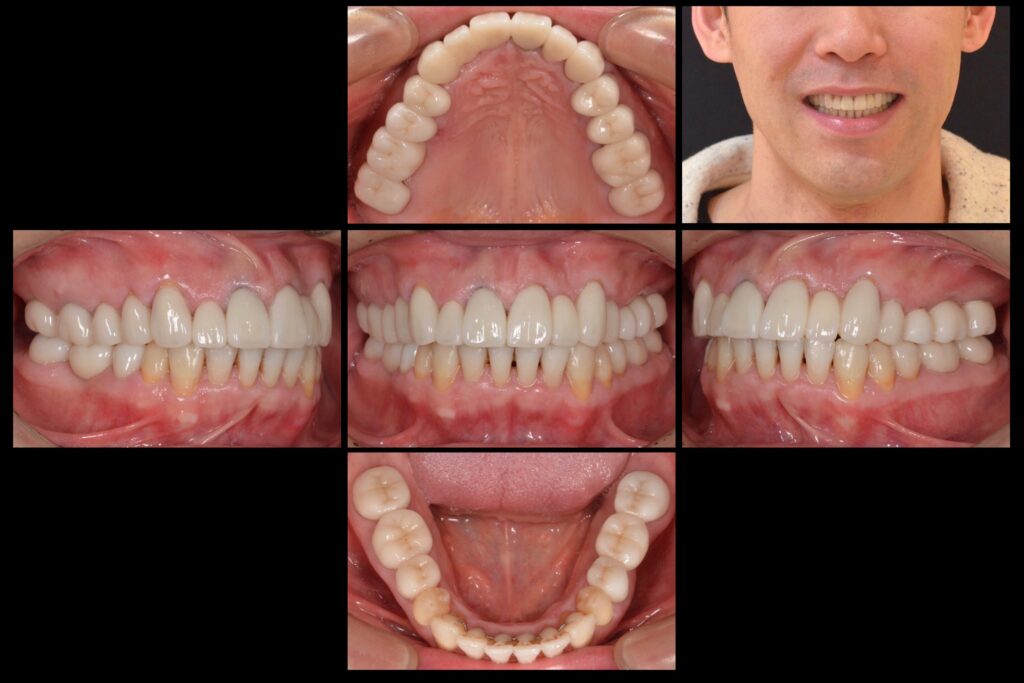

長年の悩みだった顎の痛みが無くなり、肩も軽くなりました。

前歯は仮歯で調整した物と同じ長さにしていただき、

ホワイトニング色を選んだので色も形も気に入っています。

私の中では、人生が変わる治療でした。

| 主訴 | 虫歯と歯並びを治したい |

| 診断名 | 2次う蝕・不正咬合 |

| 年齢 | 40代男性 |

| 治療方法 | セラミック治療・矯正治療 |

| 抜歯部位 | 左上6番残根抜歯 |

| 治療期間 | 一年 |

| 治療費 | 20万円/1本 |

| リスク 副作用 | 治療終了後のメンテナンス不足による歯周病 歯ぎしりや過剰な噛み締めによるセラミックスの破折や歯の根の再治療 |